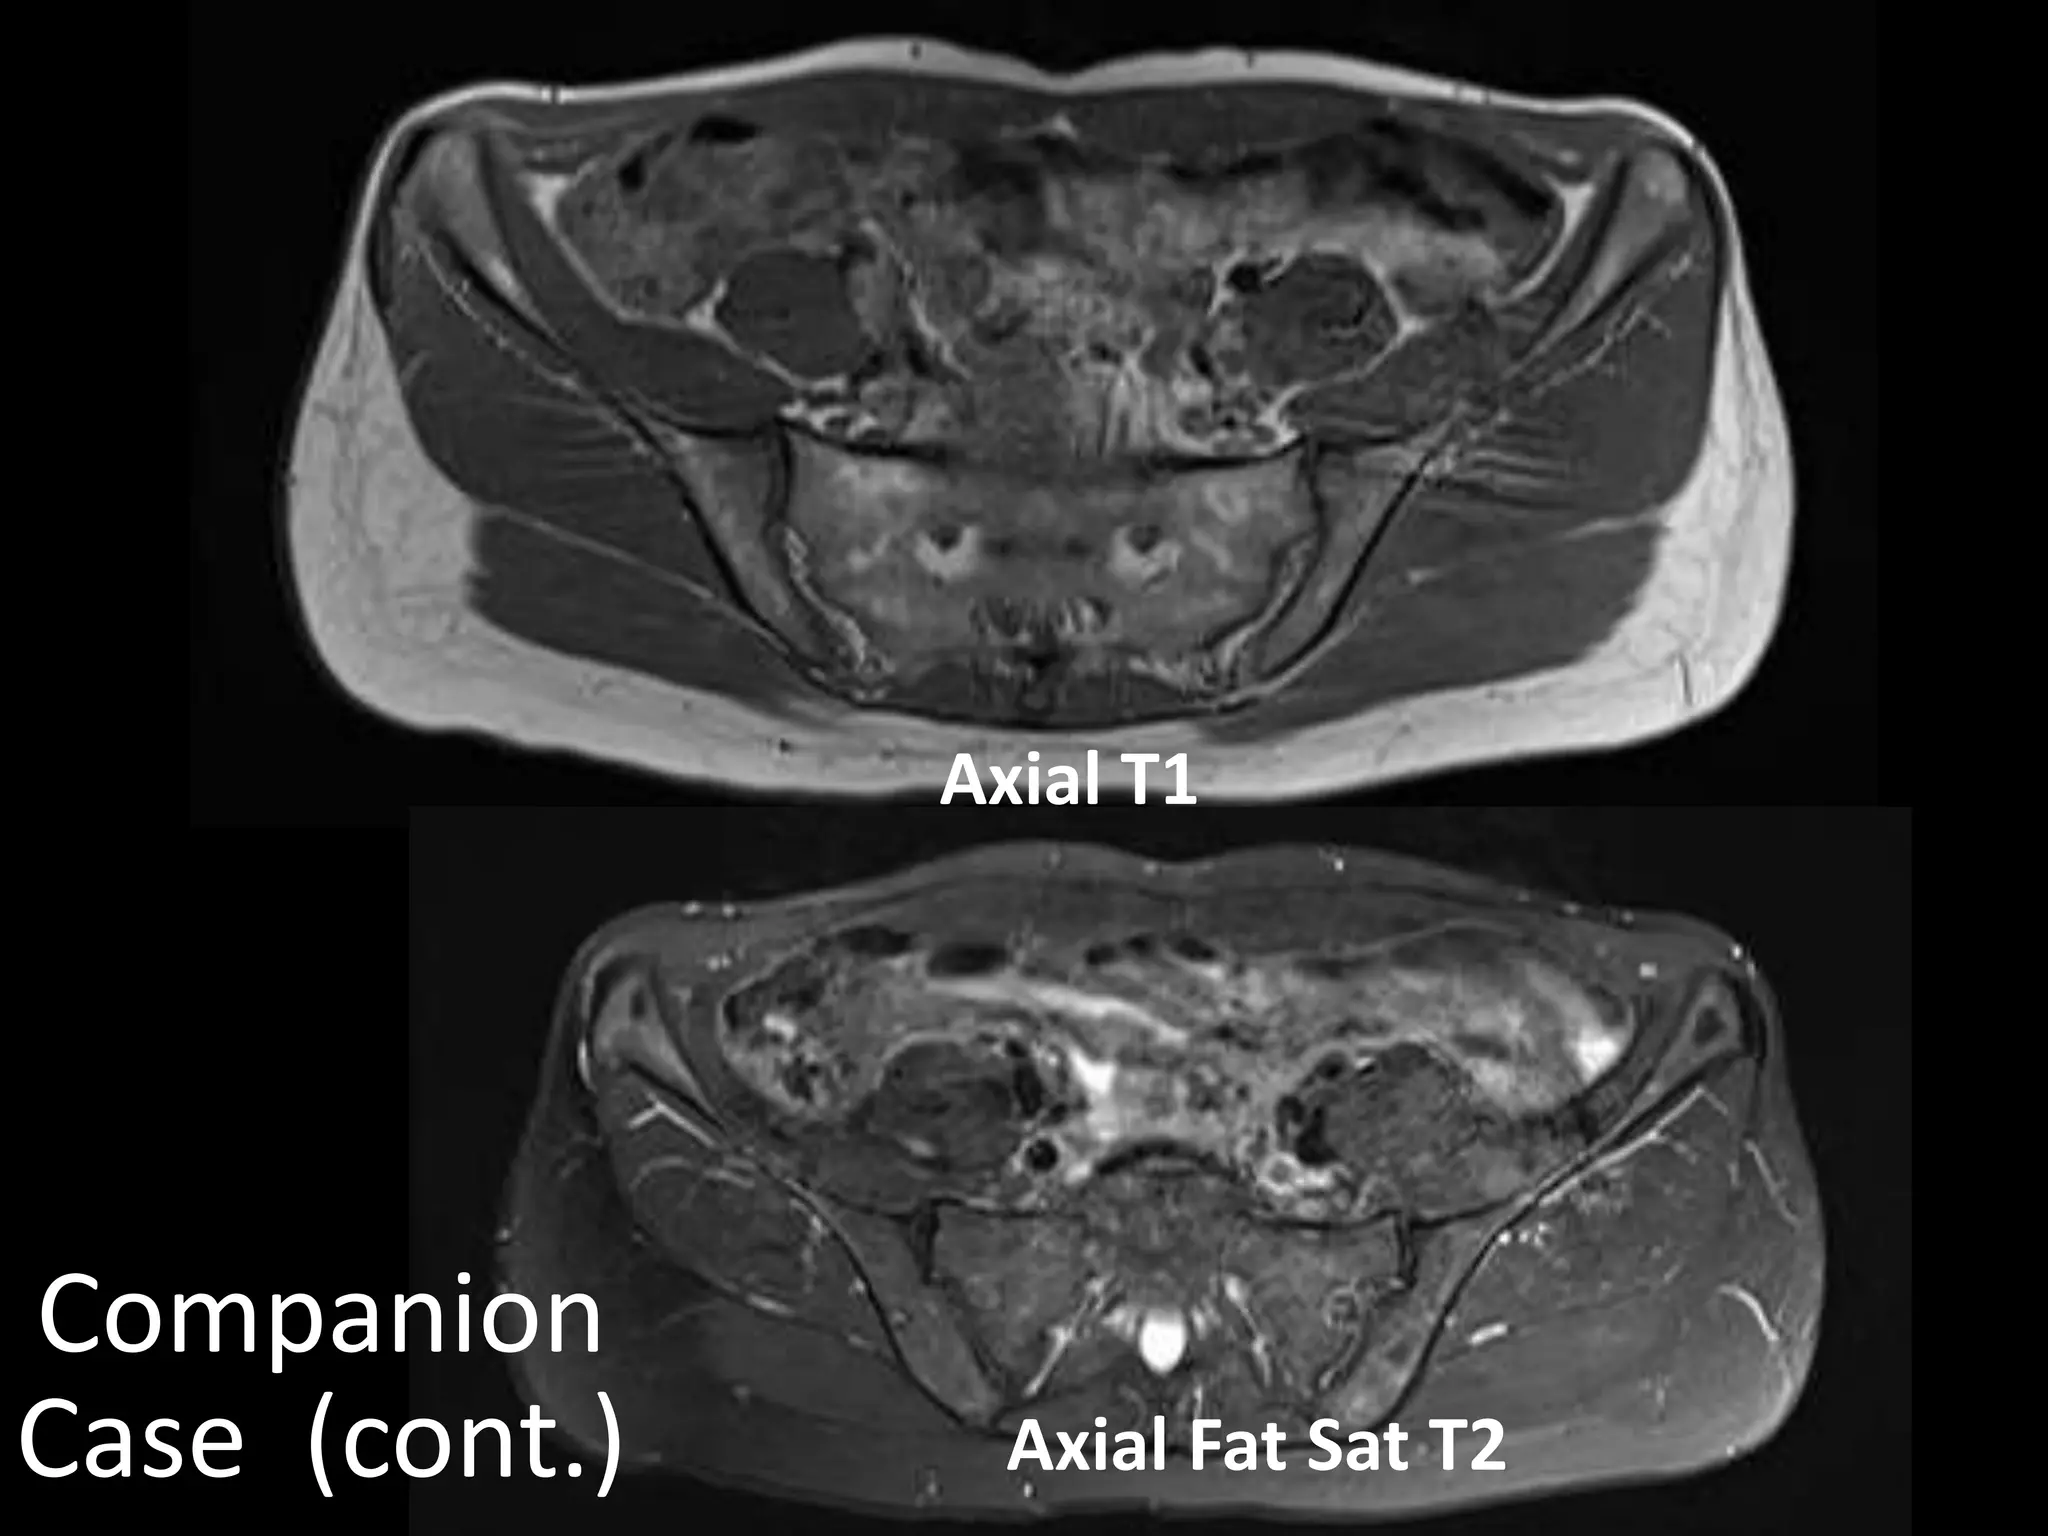

Companion Case – Different Patient

43 yo woman, very athletic

focal pain at right anterior superior iliac

crest

Coronal Fat Sat T2

Axial T1

Companion

Case (cont.) Axial Fat Sat T2